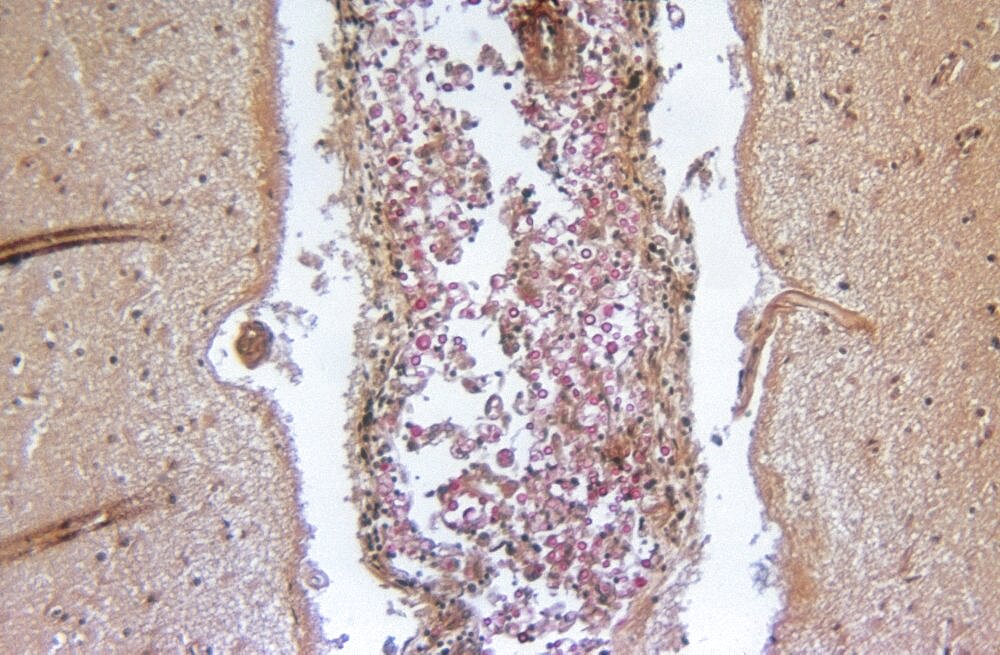

Preview Cryptococcosis, LM Image ID: 1349-405 Artist: CDC Purchase a commercial license Buy framed prints & more from our print store cell cells cryptococcal meningitis cryptococcosis disease fungus histology illness infection microbiology mucicarmine stain mucicarmine stains pathogen science single cell single cells unicellular